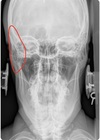

NASIUM ANATOMICAL LANDMARKS

upper teeth

54

medial inferior tip of condyle

55

Nasium view

nasal septum + spine

56

transverse process of c1-c3

57

lower teeth

58

spinous process c2-t1

59

nasal aperture

60

maxillary sinus

61

frontal sinus

62

mastoid (air cells) process

63

lateral mass c1

64

occipital-atlantal joint space

65

atlantal-axial joint space

66

mandible body

67

mandible ramus

68

mandible angle

69

mandible mentum

70

odontoid process

71

articular pillar